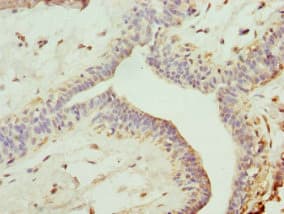

Rabbit Polyclonal TRIM13 antibody. Suitable for WB, IHC-P and reacts with Human samples. Cited in 3 publications. Immunogen corresponding to Recombinant Fragment Protein within Human E3 ubiquitin-protein ligase TRIM13 aa 1-350.

Applications IHC-P, WB